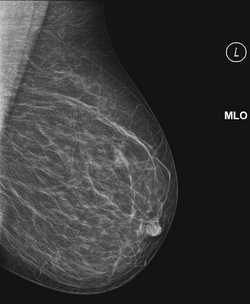

По показаниям врач-маммолог может назначать рентгеновскую маммографию. Однако для молодых женщин и обладательниц небольшой груди предпочтительнее ультразвуковая маммография.